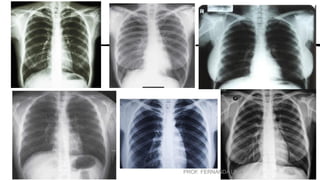

CRITÉRIOS DE

AVALIAÇÃO

ANATOMIA DEMONSTRADA

• São observados ambos os pulmões, dos ápices até

os seios costofrênicos e a traqueia, preenchida por

ar, do nível da T1 para baixo. • As sombras hilares,

o coração, os grandes vasos e a caixa torácica são

evidenciados.

POSIÇÃO

• Queixo suficientemente elevado para impedir sua

superposição sobre os ápices. • Rotação anterior

dos ombros o suficiente para impedir a

das escápulas nos campos

superposição

pulmonares.

EXPOSIÇÃO

• Sem artefato de movimento, evidenciado pelos

contornos bem definidos das costelas, diafragma,

e da silhueta cardíaca. • Contraste com ampla

escala de tons de cinza objetivando a visualização

da fina trama vascular nos pulmões.